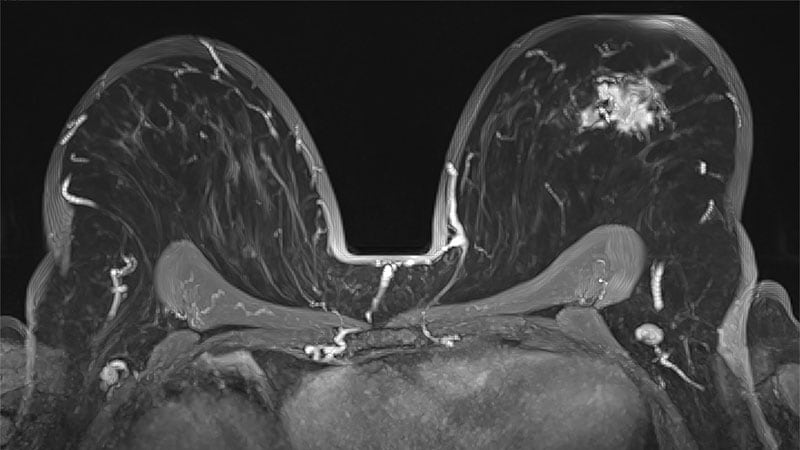

Who’s at Higher Risk for Breast Cancer Recurrence?

When it comes to a woman’s risk for a breast cancer recurrence, hormone status appears to matter.

New research shows that patients with ER-negative disease have a higher risk of a second breast cancer within a 5-year window post-diagnosis compared with patients with ER-positive disease.